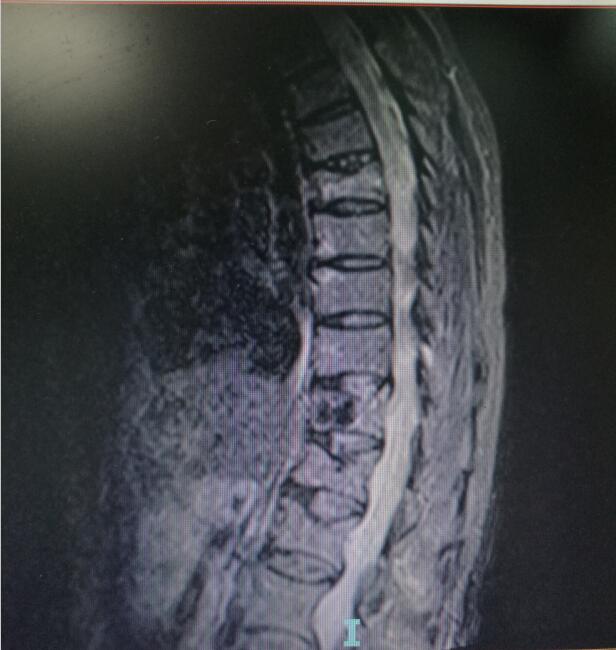

術(shù)前MRI(核磁共振檢查)